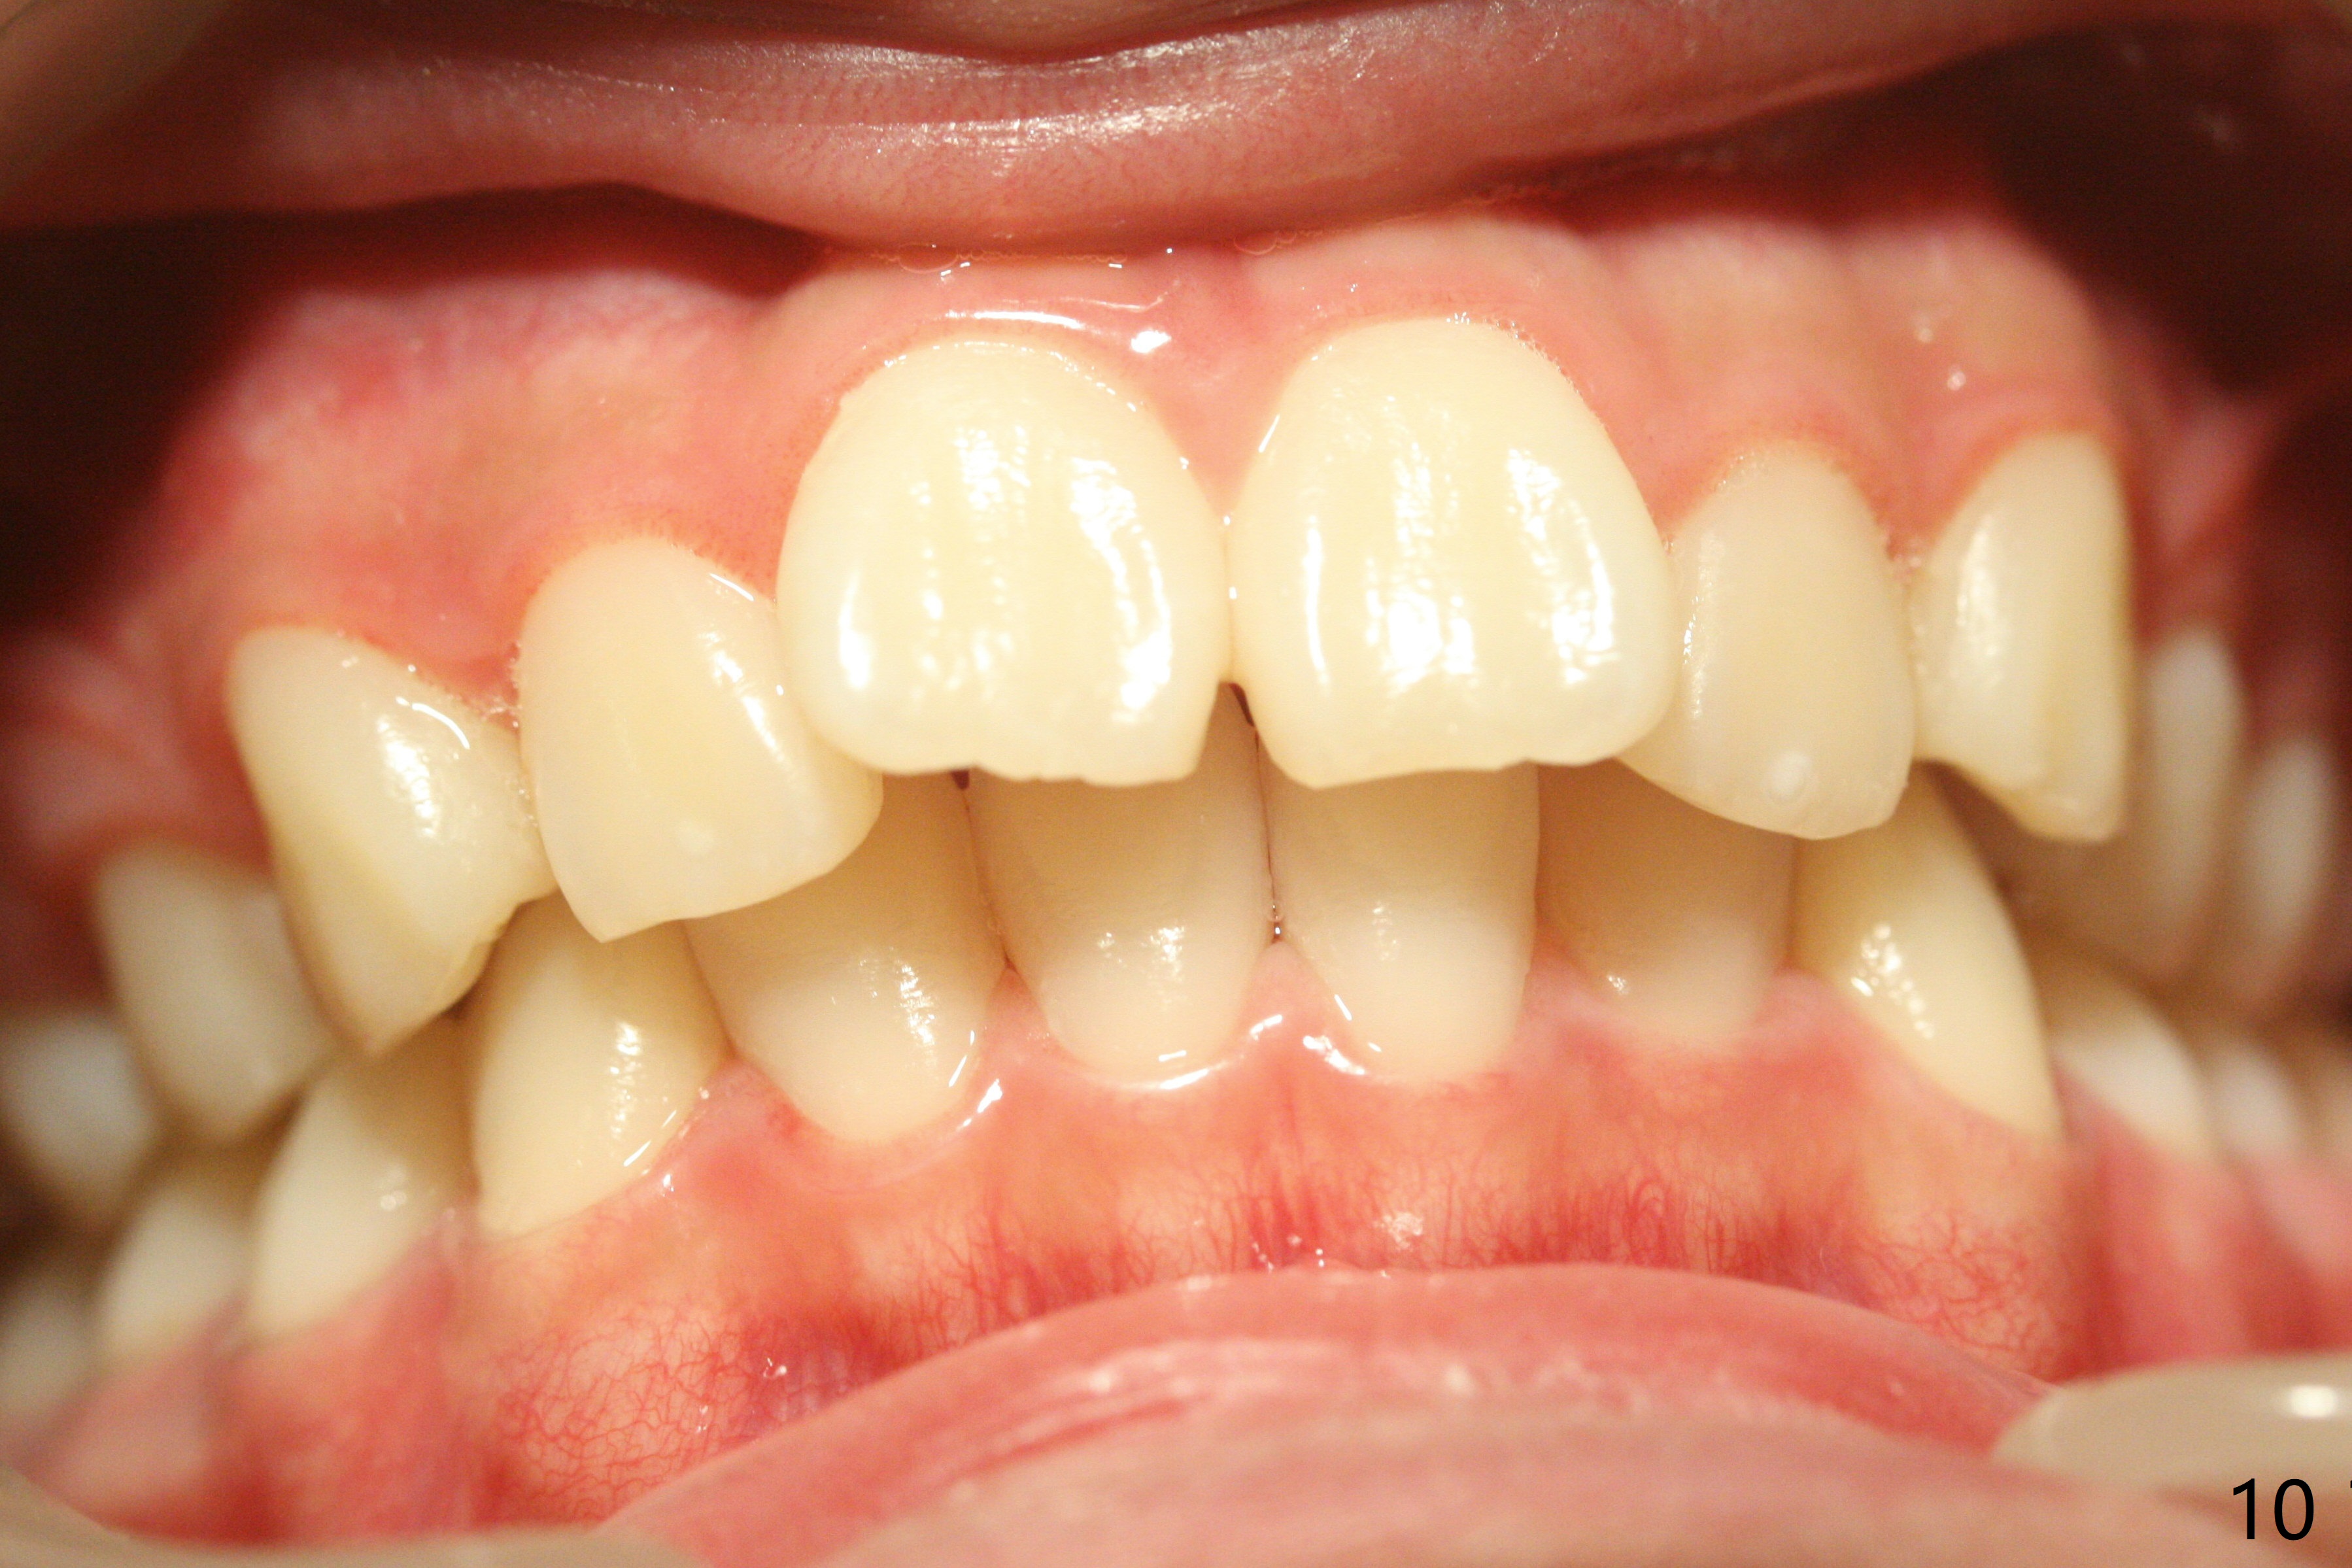

Facial Class I Occlusal Class II

A 12-year-old woman has Class I facial profile (Fig.1-4,12,13) and apparently Class II Division I malocclusion (Fig.6-11). Start Class II retraction as early as possible to take advantage of the upper and lower posterior diastemata (Fig.9,11 (in fact there is no diastema)). LL7 impaction is noted immediately prebanding (Fig.14). Surgical access is pending.